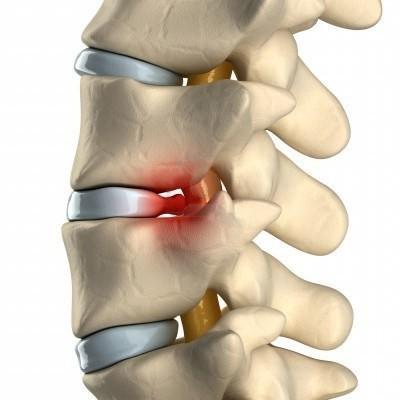

• Остеохондроз – процесс разрушения межпозвоночного диска, при котором позвонки сближаются, защемляя нервы. Обостряется сезонно, после гиподинамии, нагрузок. Боли длительные, средней интенсивности, разлитые. Схожая симптоматика, обычно, наблюдается и в суставах других групп;

• Грыжа, протрузия межпозвоночного диска – выход диска или его содержимого за пределы позвоночного столба, в спинномозговой канал. Происходит сдавливание большого количества нервной ткани, потому кроме очень интенсивных болей наблюдаются онемения ног, гипертонус, спазм мышц в них, их слабость;

Остеохондроз

Возникновение тянущих болей в пояснице и в паху нередкое явление, если у вас начался остеохондроз в нижнем отделе спины. Это состояние проявляет себя тем, что хрящевая ткань становится не такой плотной, а сами хрящи – более тонкими и не справляются со своими функциями. Причины могут заключаться в малой подвижности, ожирении, монотонных нагрузках на спину и пр.

Межпозвоночная грыжа

При грыже боли проявляются в момент нагрузки на поясницу. Они имеют острый «простреливающий» характер, и только спустя время болевой синдром «спускается» в низ живота.

При сидении болит в паху и спинаМежпозвоночная грыжа считается последствием остеохондроза. Представляет собой выпячивание позвоночных дисков. При пальпации ощущается небольшая боль, физические нагрузки противопоказаны.

Поясничные грыжи обычно находятся между третьим, четвертым и пятым поясничными позвонками и между пятым позвонком и крестцом. Зачастую грыжей защемляются нервы, ведущие в нижние конечности. Боль при межпозвонковых грыжах острая. Больному тяжело нагибаться, вставать, порой даже лежать на ровной поверхности.